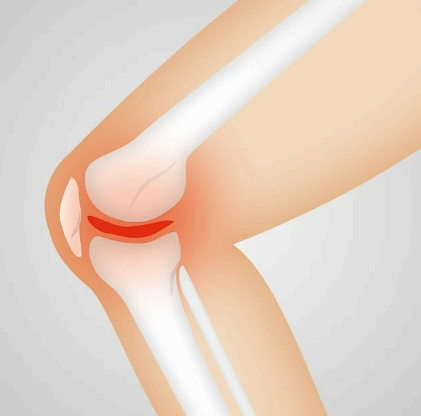

콘드로이친은 그리스어로 관절이라는 뜻이며 콘드로이친은 관절과 연골을 구성하는 주요 성분 중 하나입니다. 관절과 연골의 구성 주요 성분은 콘드로이친, 글루코사민이 대표적인데 이러한 콘드로이친은 나이가 들 수록 점점 감소하여 꾸준히 콘드로이친 섭취하여 관절 건강을 챙겨주어야 합니다.

노화가 진행되면서 연골의 노화와 손상으로 염증과 통증이 발생되게 되는데 이러한 연골의 1/3을 차지하는 핵심성분이 콘드라이친이라고 생각하시면 편리합니다.

위에 사진 중 노란색으로 되어있는 연골과 연골 사이의 매트릭스 구조의 역할을 하는 연골 탄성섬유의 주성분이 콘드로이친으로 관절 윤활제로써 연골의 마모를 감소시키며 연골 세포 생존에 필요한 영양공급을 성분입니다.